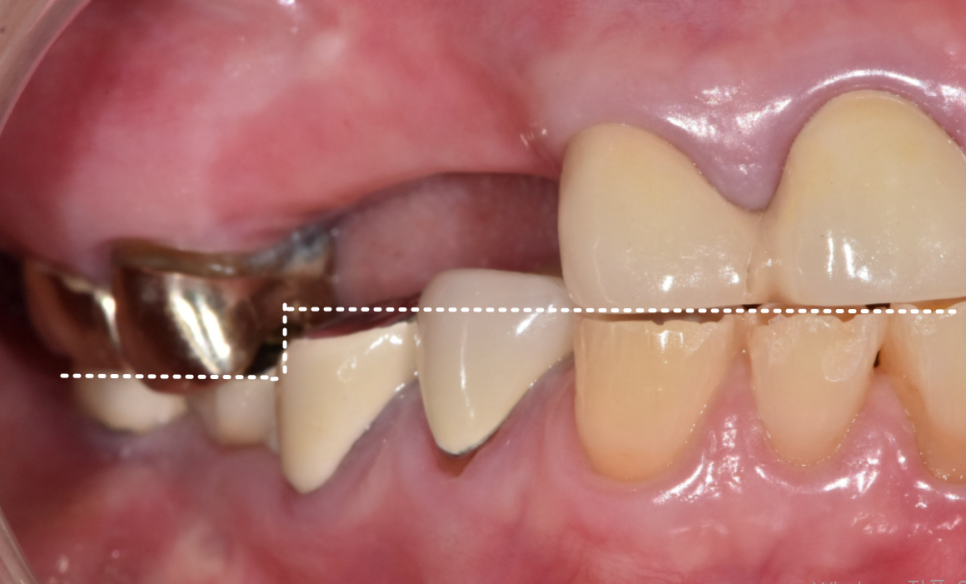

먼저, 문제의 시작이 된

오른쪽 아래 임플란트 보철을 제거했습니다.

너무 낮게 만들어진 보철을 빼고,

다른 치아들과 조화를 이루도록

좀 더 높이를 살려 다시 제작하기로 했습니다.

다음으로,

많이 닳은 아래 앞니 7개를 살려보기로 했습니다.